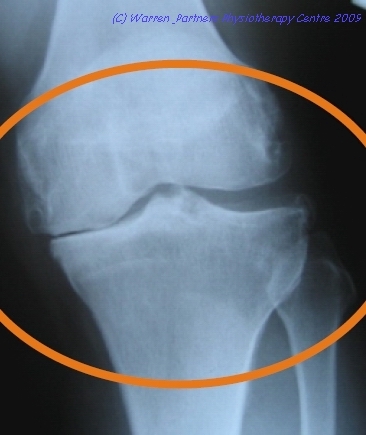

膝部關節的結構(圖一)

膝部是人體最複雜的關節之一,它是由大腿股骨、小腿的脛骨及腓骨所組成。膝關節的周圍有內側及外側韌帶及內裡的十字韌帶連接各骨髂部份。膝關節中間部份有兩片C形的軟組織—半月板,依付在脛骨的上端,它不但使關節造成鍋形以承托股骨的末端,增加關節的穩定性,更有吸收震盪力的功能。在膝部的前端,有俗稱”菠蘿蓋”的臏骨,臏骨的作用就像滑輪,連接著大腿的四頭肌,並連接在小腿脛メ突上,令膝部以較少的力量活動。

骨關節炎是一種普遍的關節疾病,是一種關節退化的現象,當膝部患上骨關節炎,會逐步出結構變化(圖二),包括:

(一) 膝關節軟骨磨損

(二) 膝關節空間收窄

(三) 軟骨下的硬骨受磨損

(四) 骨質增生(俗稱骨剌)

(五) 膝關節外觀腫大、變形

關節面的軟骨是一種十分堅韌、有彈性及耐用的軟組織,但由於軟骨缺乏良好的血液循環,它只能靠關節囊內液體輸送所需的營養及氧氣,所以隨著年齡增長,新陳代謝減慢,令磨損之軟骨不易復元。